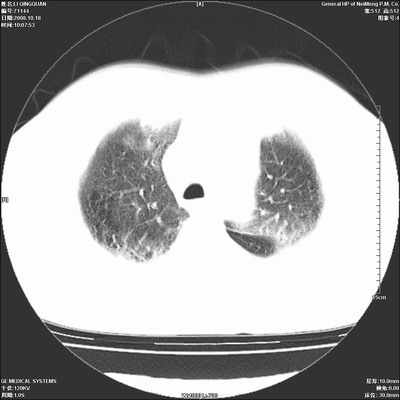

以下是引用duguo在2008-10-19 13:59:00的发言:[br]左肺上叶支气管狭窄,首先考虑中心型肺癌伴阻塞性肺炎\\肺不张.

以下是引用ybing在2008-10-19 12:58:00的发言:[br]左肺上叶阻塞性炎症-建议支气管镜进一步检查除外中央型肺癌

以下是引用随光逐影在2008-10-19 14:31:00的发言:[br]考虑左肺中央型肺癌并左肺上叶阻塞性肺炎,肺不张。